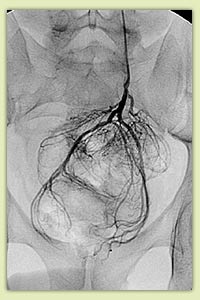

Варикоцеле: патологический кровоток по семенной вене (А); окклюзия вены через 30 мин после введения склерозанта (Б) |